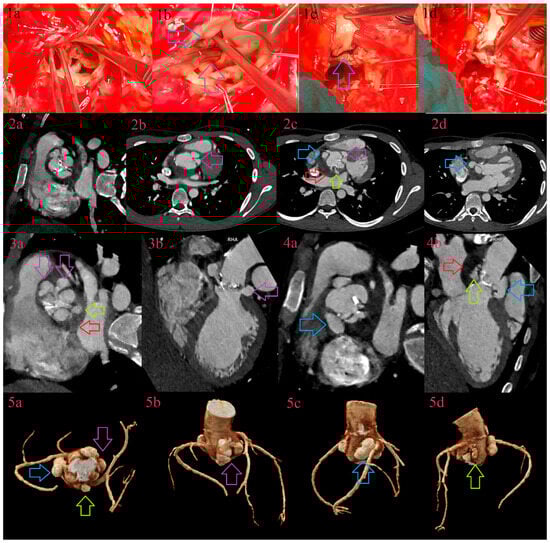

3.7. Pseudoaneurysms

3.8. Fistulas

3.9. Leaks

3.10. Image Quality Improvement